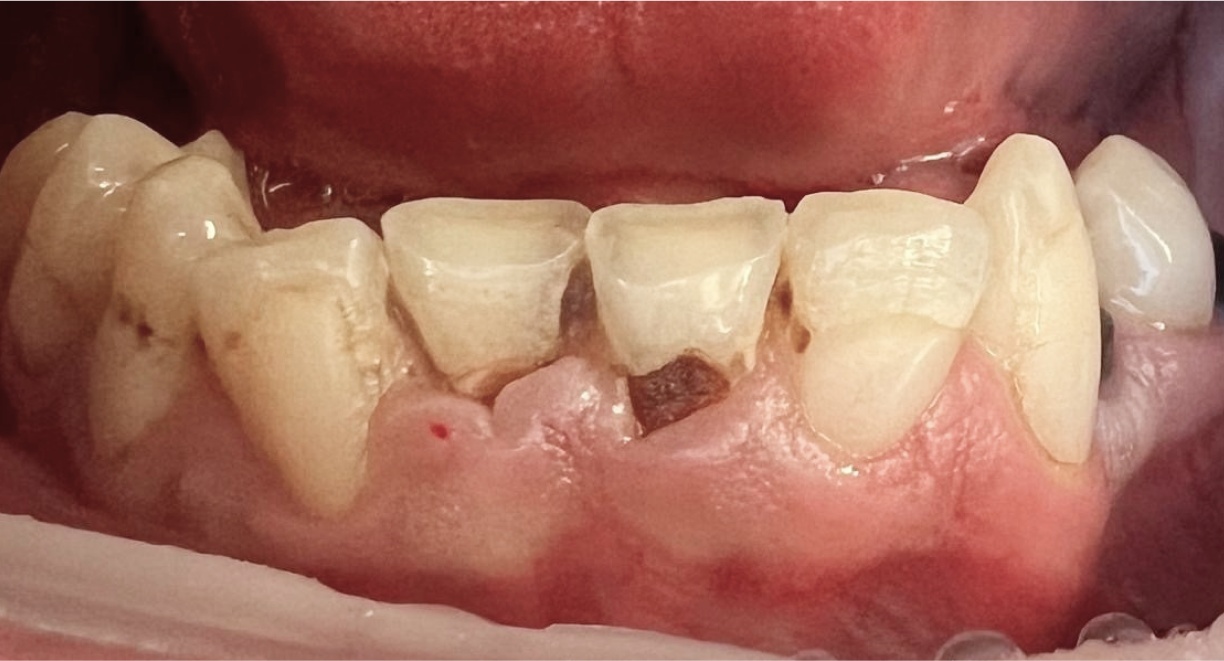

• Tooth Restoration and Caries Treatment

The patient underwent caries treatment and replacement of old fillings, carefully restoring the natural shape, colour, and function of the teeth. High-quality materials were used to achieve a seamless blend with the natural tooth structure and an aesthetically refined appearance. This treatment helps maintain oral health and prevents further tooth decay.

Doctor: Anna Petrova